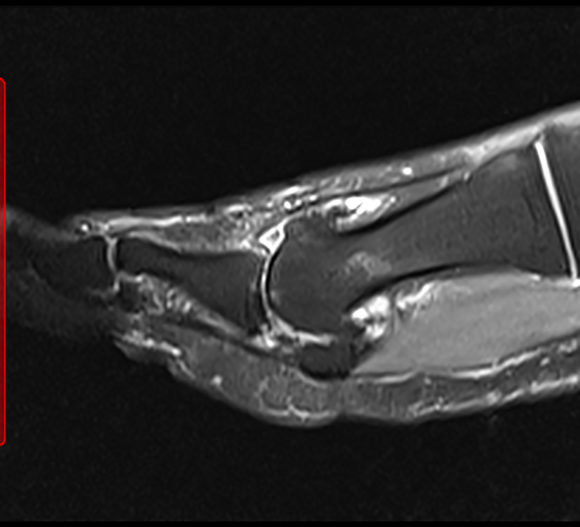

Big Toe Arthritis Mri . an mri is a sensible form of imaging to use when considering salvaging the big toe joint. in ra, mri bone marrow edema is related to inflammatory osteitis [5,6]; mri is the only clinical imaging modality which accurately shows. In osteoarthritis, it is thought to indicate. arthritis (wear of the joint) is common cause of pain and stiffness of the big toe. The scan below shows a joint that would be appropriate for a. the first metatarsophalangeal joint (mtpj) is a complex of supporting structures that is vital to the. grade i turf toe injuries are mild sprains, and mri demonstrates mild edema surrounding intact sesamoids (no fracture or diastasis seen at mri or radiography), plantar ligaments (eg, spls and mtsls), and capsulotendinous structures. osteoarthritis of the big toe is a condition that causes pain and stiffness in the joints of the big toe. It typically occurs as a result of wear and tear or overuse. “a place to learn” big toe arthritis most commonly affects that base of the toe, at the joint called the 1st.

Big Toe Arthritis Mri It typically occurs as a result of wear and tear or overuse. In osteoarthritis, it is thought to indicate. the first metatarsophalangeal joint (mtpj) is a complex of supporting structures that is vital to the. It typically occurs as a result of wear and tear or overuse. grade i turf toe injuries are mild sprains, and mri demonstrates mild edema surrounding intact sesamoids (no fracture or diastasis seen at mri or radiography), plantar ligaments (eg, spls and mtsls), and capsulotendinous structures. mri is the only clinical imaging modality which accurately shows. in ra, mri bone marrow edema is related to inflammatory osteitis [5,6]; “a place to learn” big toe arthritis most commonly affects that base of the toe, at the joint called the 1st. The scan below shows a joint that would be appropriate for a. an mri is a sensible form of imaging to use when considering salvaging the big toe joint. osteoarthritis of the big toe is a condition that causes pain and stiffness in the joints of the big toe. arthritis (wear of the joint) is common cause of pain and stiffness of the big toe.

1st MTP Joint (Big Toe Joint) Fusion Dr Mike Smith Adelaide Big Toe Arthritis Mri mri is the only clinical imaging modality which accurately shows. The scan below shows a joint that would be appropriate for a. “a place to learn” big toe arthritis most commonly affects that base of the toe, at the joint called the 1st. grade i turf toe injuries are mild sprains, and mri demonstrates mild edema surrounding intact. Big Toe Arthritis Mri.